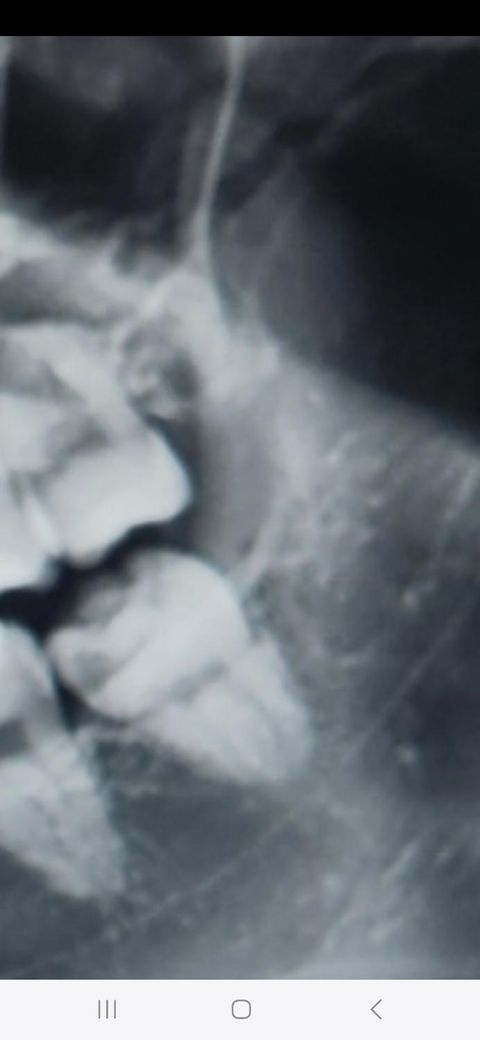

• 1번 째 사진

위,아래 두개는 보통 같이 뽑는것이 일반적입니다. 위, 아래 사랑니도 뿌리가 심하게 휘어있거나 매복되어있진 않아서 오래걸리진 않을 것 같습니다.

환자 분의 선택이라고 보시면 됩니다. 보여주신 사진상으로는 2개 모두 뽑는데 크게 어려움은 없어 보입니다. 하지만 불편감을 느끼는 정도 등에 따라서 2개 모두 뽑았을 때 한 동안 불편감이 오래갈 수 있어 너무 불편감이 클 것으로 예상되거나 치과에 대한 공포감이 크다면 1개씩 뽑는것도 추천드립니다.